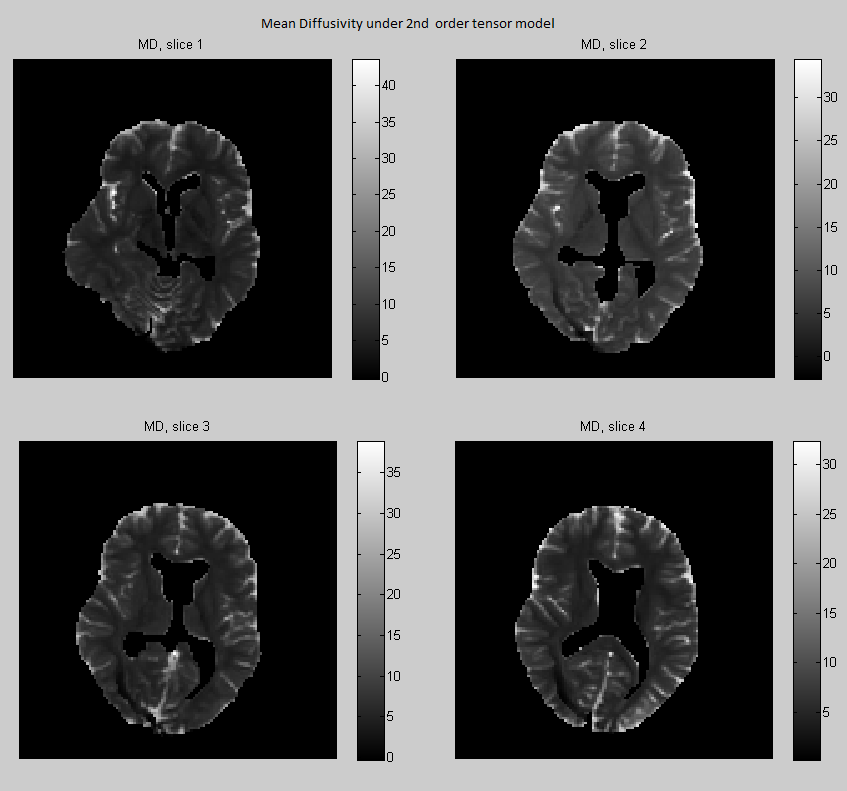

Fractional anisotropy (FA) measures the degree of anisotropy, while mean diffusivity (MD) is the average of the diffusivity function over the unit sphere. Both measures are used as biomarkers to study brain pathologies. These quantities are expressed in terms of the eigenvalues of the 2nd order tensor as

In Section 3.9 we have seen that there is a linear bijection between the tensor coefficients and the coefficients of the truncated spherical harmonic expansion of the diffusivity. This implies that we can map linearly a 4th-order tensor to a 2nd-order tensor as follows (see Özarslan E., Mareci T.H. (2003)):

and the mean diffusivity can be also expressed in terms of the 4th order tensor coefficients as

| (4.26) |

where was defined in Eq. (3.18). In Fig. 11 and 12 we compare the respectively the Bayesian estimates of FA and MD derived under the 2nd and 4th-order tensor models.